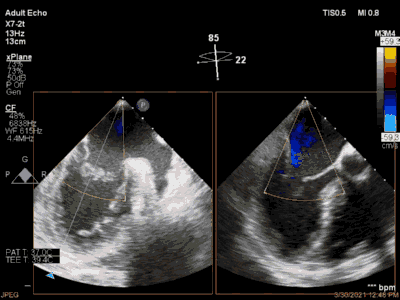

3月30日患者先在全麻下进行TEE(经食道超声心动图)再次评估瓣膜情况(视频4、视频5、视频6 ),确定为二尖瓣前组乳头肌断裂致二尖瓣前瓣脱垂并重度返流,其脱垂部位、瓣叶结构、瓣口面积等适合进行二尖瓣夹合术。术中IABP辅助,ECMO湿备,穿刺右侧股静脉,在TEE指导下顺利穿刺房间隔,随后送入二尖瓣夹合系统,在超声指导下于二尖瓣A2/P2区植入一枚Mitraclip XTR夹合器(视频7),术后TEE评估返流程度从5+降至1+(视频8 ),夹合结果满意,二尖瓣呈双孔启闭(视频9 ),术后二尖瓣平均跨瓣压差1mmHg(图1),收缩期肺静脉返流消失(图2 ),手术总耗时80min。香港亚洲医疗中心林逸贤教授通过视频连线进行手术全程技术支持。

视频4

视频5

视频6